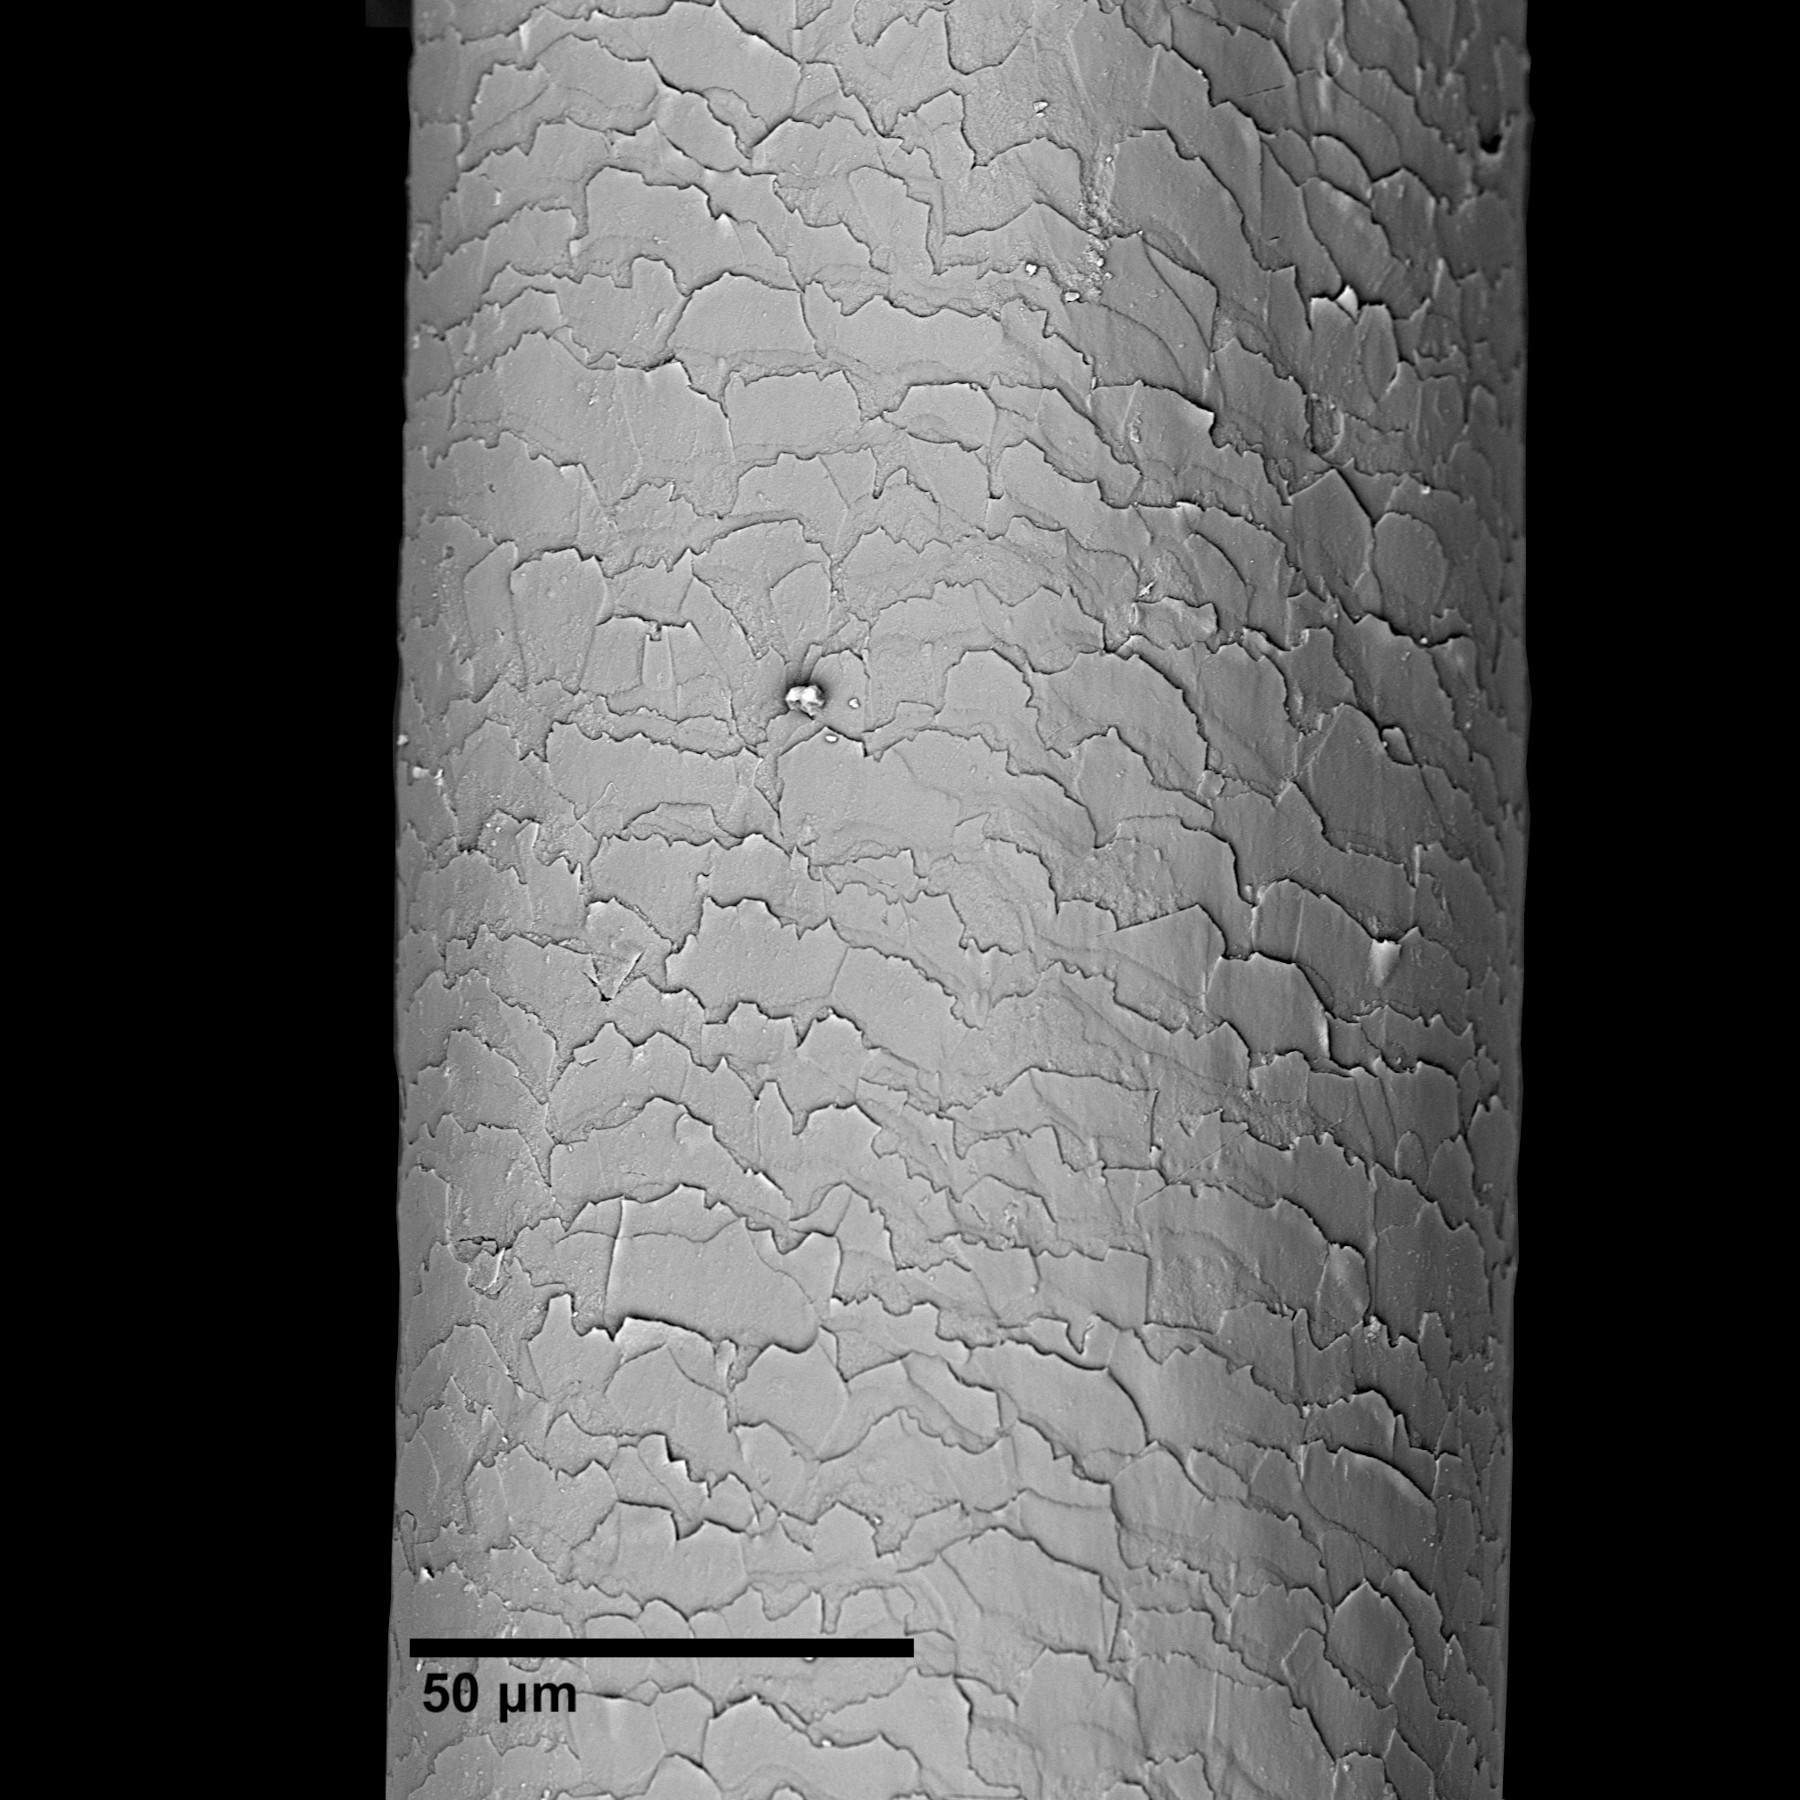

Inflammation and local pressure are common causes of localized acquired hypertrichosis (LAH). The vast majority of cases of LAH in this category described in the literature occurred after the patient underwent surgery or injection or had to wear a plaster cast. Localized acquired hypertrichosis usually disappears over time once the causative agent has ceased. This case report presents the case of a man who acquired LAH of terminal hair through inflammation and local pressure while working in mining for over 20 years. The statistical analysis showed no statistical difference between hair thickness from both shoulders. The photos show the hair under a scanning electron microscope.